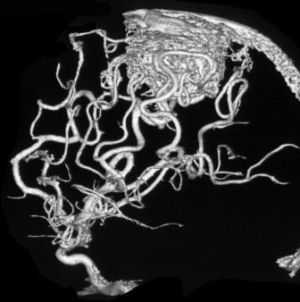

Внешне болезнь выглядит, как узлы или переплетения сферической формы и разных размеров, которые затрудняют движение крови по сосудам.

Сосудистая мальформация на МРТ